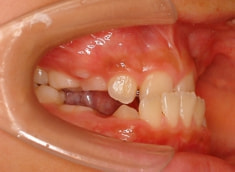

治療開始から約3ヶ月後

治療開始後3ヶ月で、すでに前歯がジャンプしていますが、ここで注意が必要です。これは前歯の傾斜で反対咬合が一時的に解消しているだけです。ここからしっかりとフェイスマスクを使用し、上顎の牽引をしなくてはいけません。

ジャンプしただけでは「治った」ことにはなりません。今後身長と一緒に伸びてくる下顎の成長に備える必要があります。